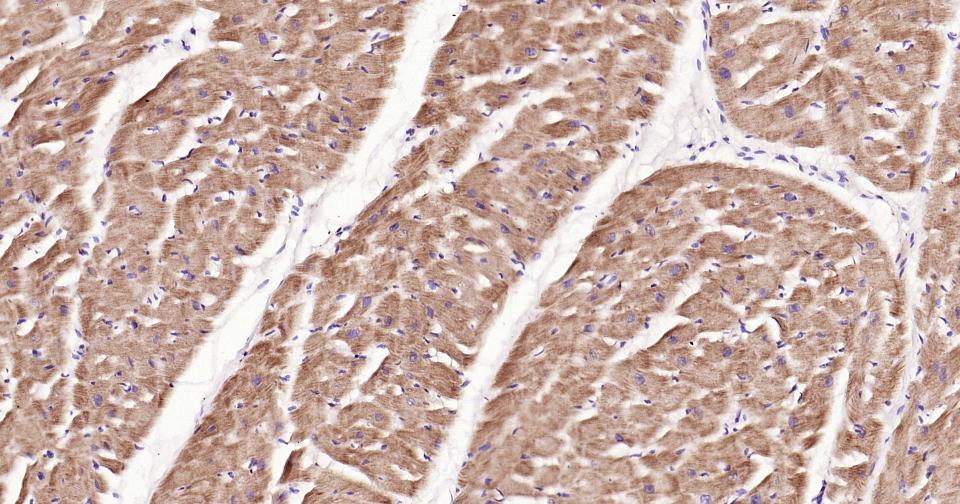

Paraformaldehyde-fixed, paraffin embedded Human Heart; Antigen retrieval by boiling in sodium citrate buffer (pH6.0) for 15 min; Antibody incubation with PIK3C3 Monoclonal Antibody, Unconjugated(bsm-61161R) at 1:200 overnight at 4°C, followed by conjugation to the SP Kit (Rabbit, SP-0023) and DAB (C-0010) staining.